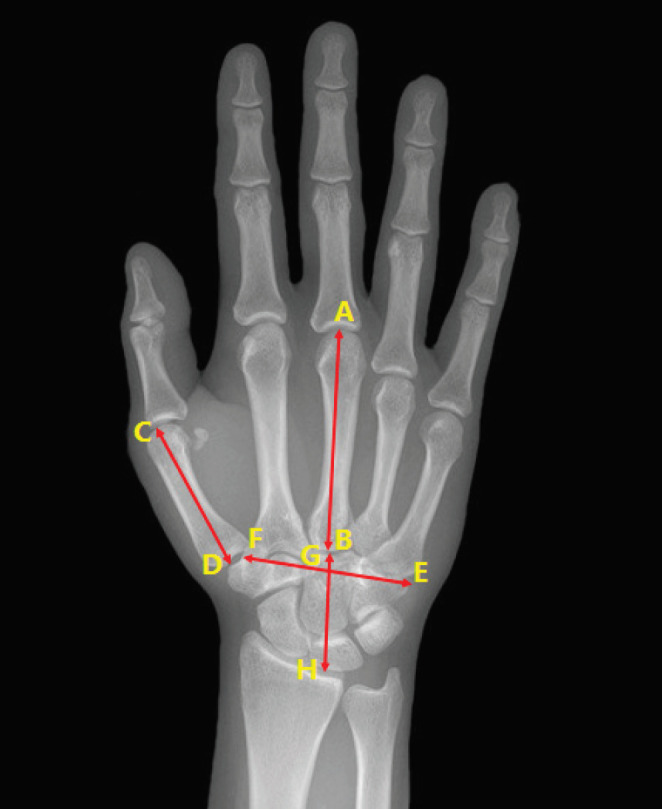

Third metacarpal length: the length between the third metacarpophalangeal joint to the middle point of carpometacarpal space line [Figure 1, AB].

Scales using for measurement of the hand radiological indices: AB: Third metacarpal length: the length between the third metacarpophalangeal joint to the middle point of carpometacarpal space line. CD: First metacarpal length: the length between the first metacarpophalangeal joint to trapezium at the first carpometacarpal joint. GH: Wrist Height: the length between the base of third metacarpal and subchondral region of the distal radius along with third metacarpus axis. EF: Hand width: transverse distance between the bases of the second metacarpus to the fifth metacarpus. AB/GH: Metacarpal length to wrist length index (carpal ratio): measured as third metacarpal length divided by palm height. AB/EF: Metacarpal length to metacarpal width index: measured as third metacarpal length divided by palm width. AB/CD: Third to first metacarpal length: measured as third metacarpal length divided by first metacarpal length

First metacarpal length: the length between the first metacarpophalangeal joint to trapezium at the first carpometacarpal joint [Figure 1, CD].

Wrist Height: the length between the base of third metacarpal and subchondral region of the distal radius along with third metacarpus axis [Figure 1, GH].

Hand width: transverse distance between the bases of the second metacarpus to the fifth metacarpus [Figure 1, EF].

Metacarpal length to wrist length index (carpal ratio): measured as third metacarpal length divided by palm height [Figure 1, AB/GH].

Metacarpal length to metacarpal width index: measured as third metacarpal length divided by palm width [Figure 1, AB/EF].

Third to first metacarpal length: measured as third metacarpal length divided by first metacarpal length [Figure 1, AB/CD].